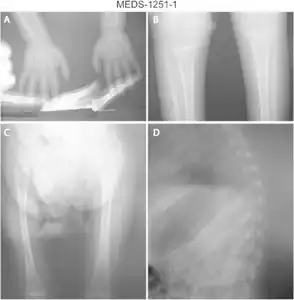

a) Osteopenia in carpal, metacarpal and phalanges b) tibia and fibula with metaphyseal widening/osteopenia c)severe osteopenia d) osteopenic ribs.